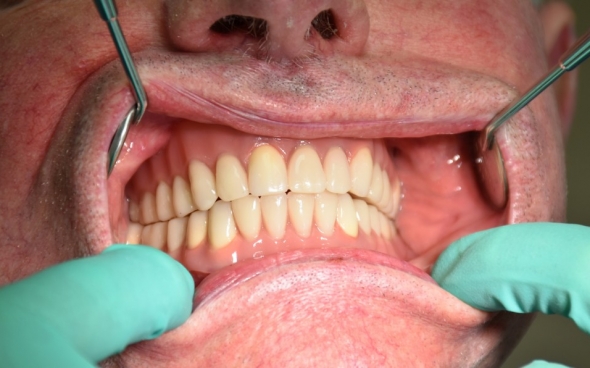

Metallkeramische Oberkiefer- und Unterkiefer-Vollbrücken

Der 48 jährige österreichische Patient erschien an unserer Zahnklinik zu einem Beratungstermin, wo eine Röntgenaufnahme und ein Kostenplan für metallkeramische Vollbrücken im Ober- und Unterkiefer mit insgesamt 25 Kronen erstellt wurden.